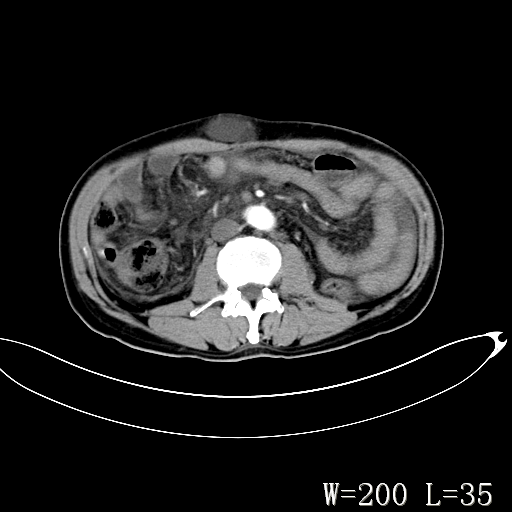

男,52岁,门脉高压断流术后1年,发现腹部肿物2月。

1)前腹壁中线区(脐上方)囊性占位性病变,考虑淋巴囊肿。2)腹水。